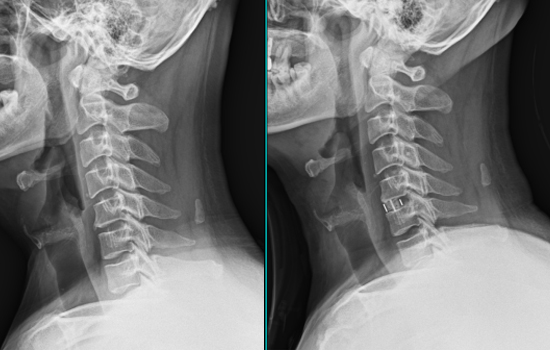

경추 미세현미경 인공디스크 치환술

목 뼈 사이에 있는 디스크가 손상되어서 본래의 기능을 상실한 경우 동일한 기능을 하는 인공 디스크를 대체하는 치료 입니다. 특수 제작된 인공디스크를 삽입하여 수술 후 목의 운동 범위를 제한하지 않아 일상 생활의 지장이 없습니다.